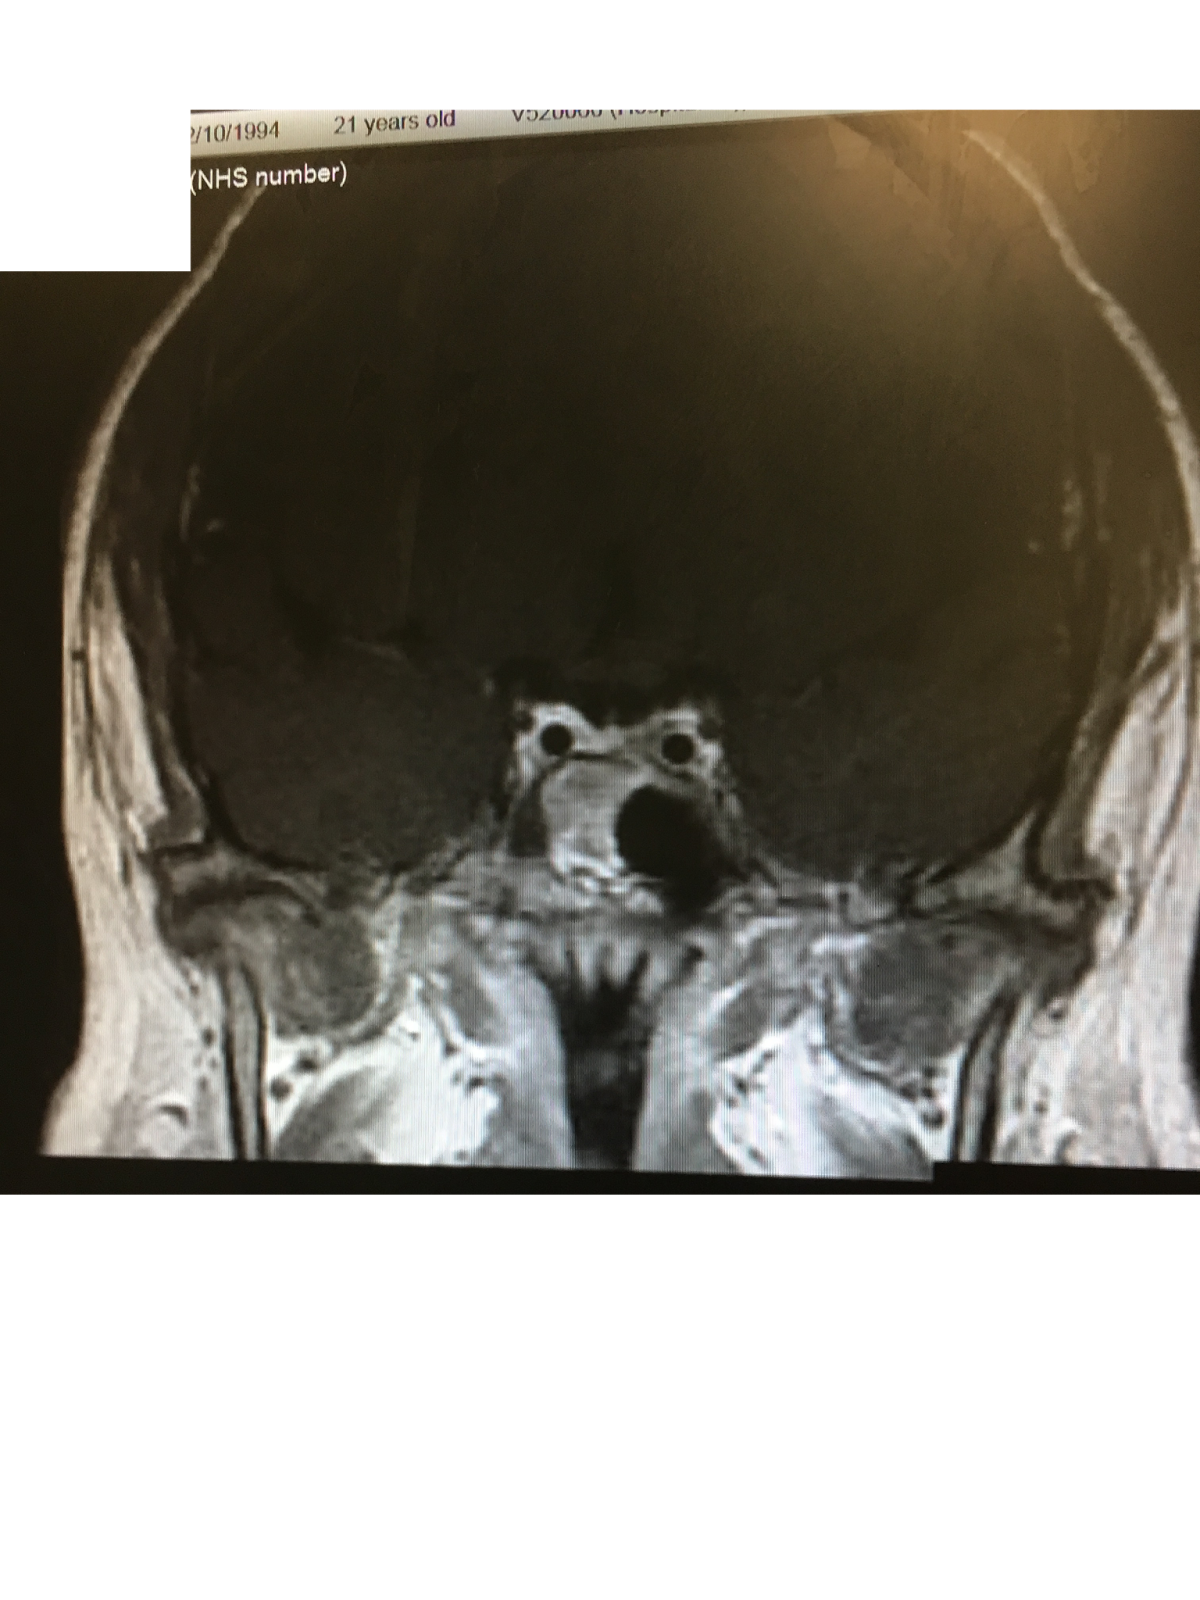

From myjourneywithcushingsdisease.blogspot.com

Fixing The Fat Girl's Future My Journey with Cushing's Disease MRI Cushing's Disease Mri — the sensitivity of mr imaging in cushing disease is not known nor is the prognostic significance of “mr. — ct or mri scans can take pictures of the pituitary and adrenal glands to see if anything shows up, such as tumors. 2 mr imaging of the. — cushing disease (cd) is associated with reduced quality of. Cushing's Disease Mri.